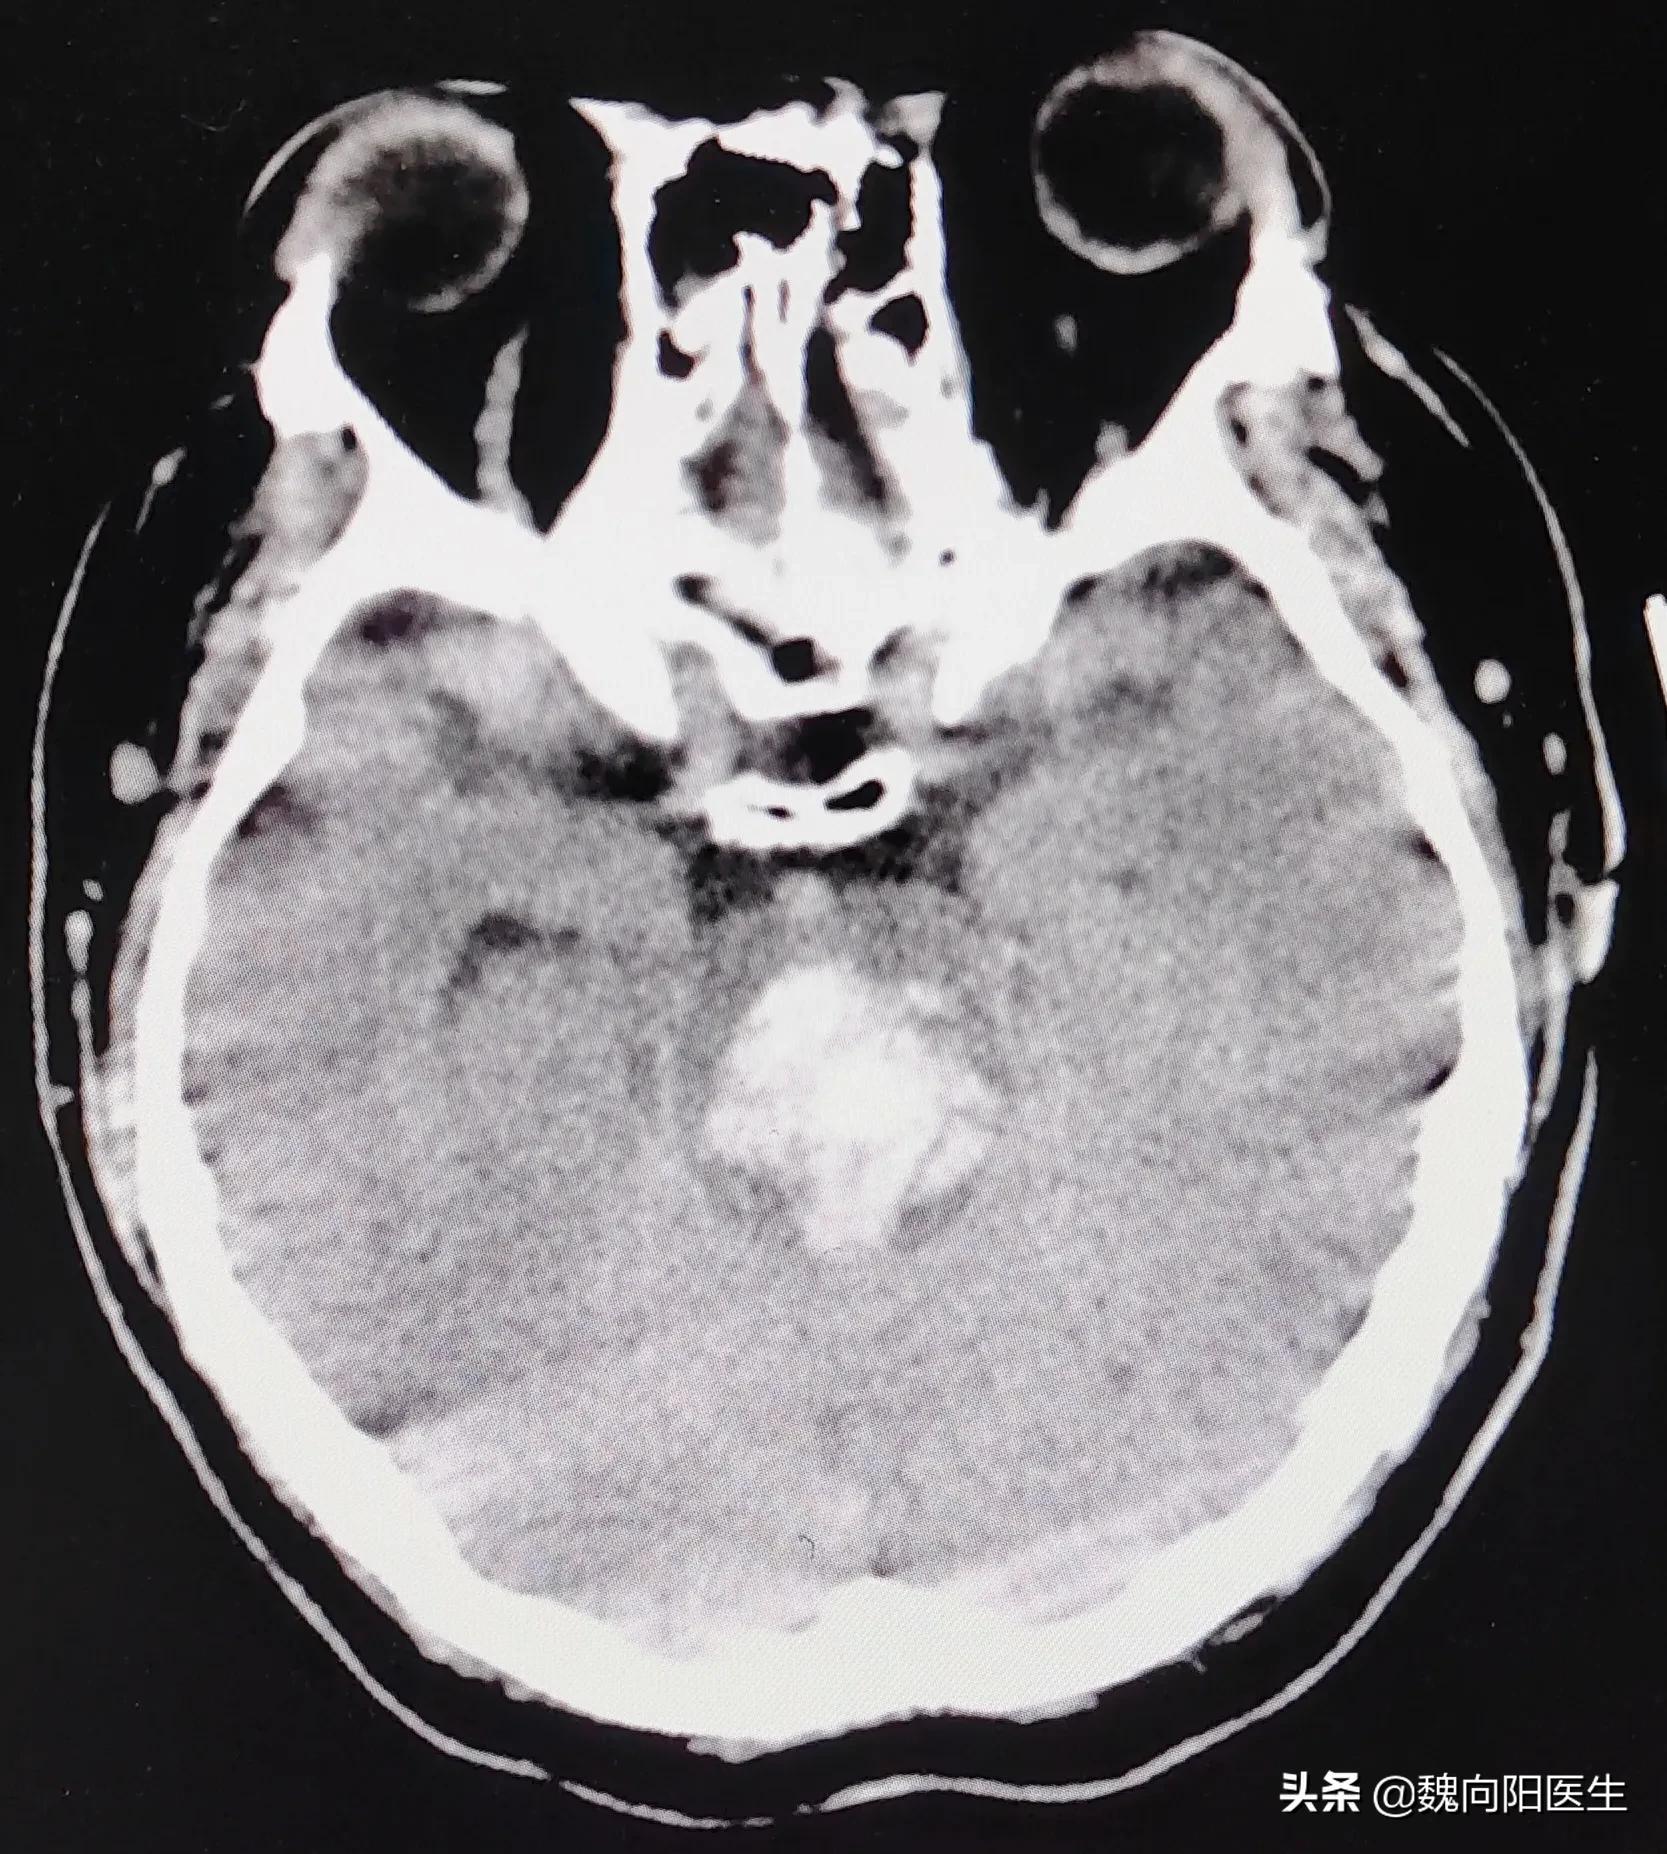

40多岁的他,因为长期没有有效控制血压,且对高血压的认识不足,并没有正规的服用降压药,最终在去年的某一天,因为脑干出血而住进了医院的重症监护室。

自从发病的那一天就一直处于昏迷状态,发病前作为一名普通的工人,默默无闻地为社会作出贡献,生活虽然不算富裕,但是过的也很充实,小日子还算幸福。